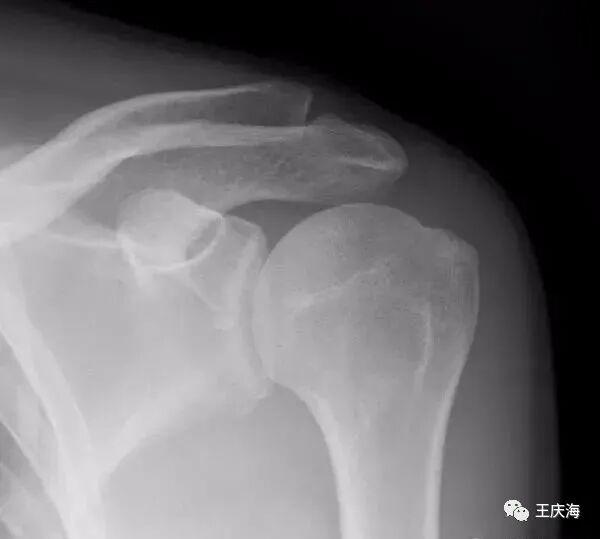

(1)X片:常规拍摄肩关节正位及冈上肌出口位X线片。典型改变包括肩峰下表面硬化和骨赘形成、大结节硬化及囊性变。通过冈上肌出口位可以评价肩峰的形状和厚度。

Bigliani将肩峰形状分为三型:Ⅰ型为平直形肩峰,Ⅱ型为弧型肩峰,Ⅲ型为钩状肩峰。

Snyder根据肩峰厚度将肩峰分为三型:Ⅰ型小于8mm,Ⅱ型8~12mm,Ⅲ型大于12mm。上述分类对于决定术中切除肩峰骨质的数量有重要意义。